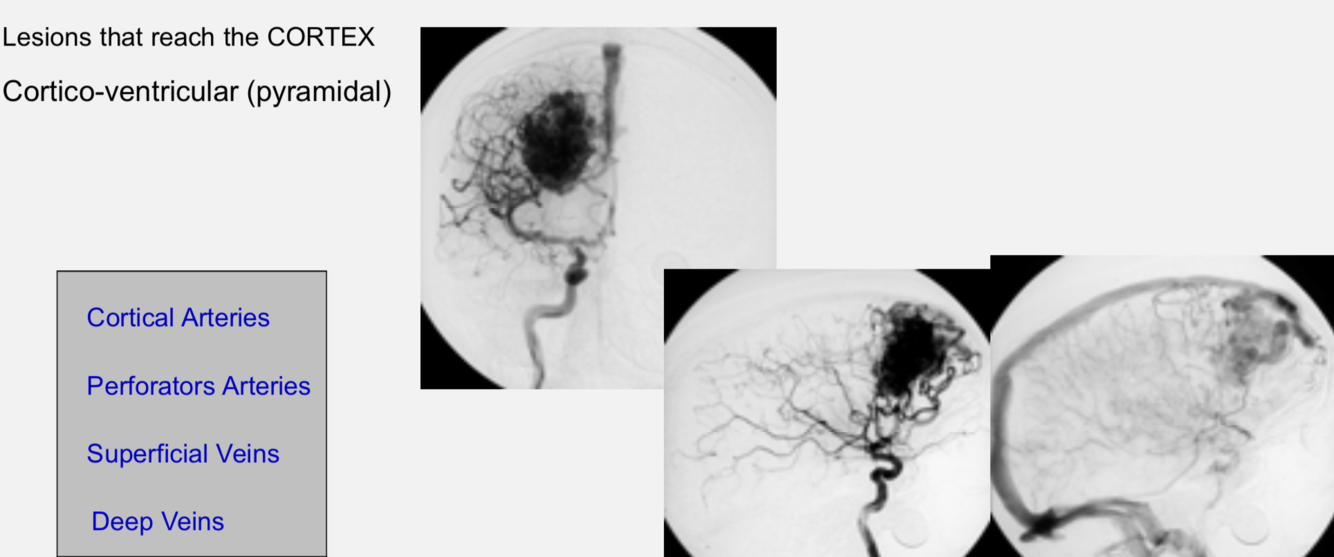

AVM - topography and vessels involved

AVM - vessels involved in cortico-ventricular avm (pyramidal)